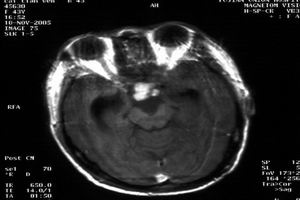

2.CT掃描顱腦CT掃描顯示為鞍區腫瘤改變,非增強掃描者實質性腫瘤表現為高密度或等密度影像,鈣化斑為高密度,囊性者因瘤內含膽固醇而呈低密度像,CT值為-40~10Hu,囊壁為等密度。病變邊界清楚,呈圓形、卵圓形或分葉狀,兩側側腦室司擴大。強化掃描時約2/3的病例可有不同程度的增強,CT值增加12~14Hu,囊性顱咽管瘤呈環狀強化或多環狀強化而中心低密度區無強化,少數顱咽管瘤不強化。一般具有鈣化、囊腔及強化後增強三項表現的鞍區腫瘤。

診斷:任何年齡的病人如出現高顱壓、神經眼科症狀及下丘腦-垂體功能紊亂均應考慮顱咽管瘤的可能。根據好發部位、臨床表現及輔助檢查診斷顱咽管瘤並不困難。凡青少年兒童出現內分泌功能障礙,如發育矮小、多飲多尿、肥胖、生殖器發育不良等,均應首先考慮本病;若有鞍上或鞍內鈣化斑,更有助於診斷。若成人出現性功能障礙或頭痛、視力視野障礙,也應考慮本病。少數臨床表現不典型者、臨床症狀輕微者診斷不易,關鍵是要提高對本病的警惕性。通過實驗室檢查、CT和MRI對診斷具有重要的意義,對疑似病例應及時做此種檢查,以免延誤診斷。實驗室檢查:普通實驗室檢查無特殊。內分泌功能檢查多數病人可出現糖耐量曲線低平或下降延遲,血T3、T4、FSH、LH、GH等各種激素下降。少數表現為腺垂體功能亢進,大多數表現為程度不等的腺垂體及相應靶腺功能減退。